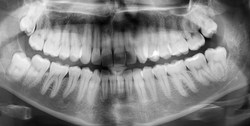

دبیر انجمن جهانی لیرز در پزشکی با اشاره به سه کاربرد اصلی لیزر در پزشکی گفت: ایران سرگروه جهانی در حوزه لیزرهای کمتوان در دندانپزشکی انتخاب شده و طی 6 ماه آینده پروتکل درمانی برای دندانپزشکان دنیا ارائه میکند. به گزارش آوای نشاط رضا فکرآزاد در نشست خبری که در ارتباط با رونمایی از جایزه علی جهان برگزار شد، اظهار داشت: لیزر به طور کلی سه کاربرد اساسی دارد که کاربرد اول در حوزه تشخیص بیماریها بوده که کمتر به آن پرداخته شده است و تشخیصضایعات عروقی، پوسیدگیهای دندانی، آنالیز نمونههای خونی، تومور داخل ریه نیز و حتی ناخن و مو از جمله استفادههای لیزر در تشخیص بیماریها است.

وی با اشاره به اینکه لیزر یک تکنولوژی و فناوری بسیار پیشرفته است که همچون برق میتوان کارهای مختلفی با آن انجام داد گفت: در کاهش دردهای دیسکهای کمر، زخم بستر و ...میتوان از لیزر استفاده کرد و امروزه گروههای چشمپزشکی، فیزیوتراپی، توانبخشی و پوست با استفاده از لیزر جهت کمک به بیماران استفاده میکنند. در حوزه زنان ودندانپزشکی نیز مورد توجه قرار گرفته است.

وی خاطرنشان کرد: تیم ایرانی در حال حاضر سرگروه جهانی برای لیزرهای کمتوان در حوزه دندانپزشکی انتخاب شده که طی 6 ماه آینده پروتکل درمانی برای دندانپزشکان دنیا ارائه میکند و در واقع این پروتکل به نام ایران ثبت میشود.